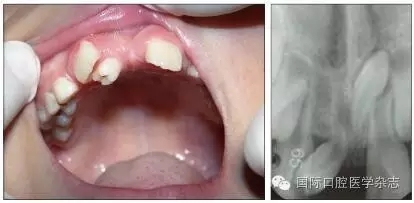

1.1.3   對牙弓長度的影響   乳牙齲病引起牙弓長度的變化并不只在乳牙因齲早失后,而是在乳牙發(fā)生鄰面齲之時即可發(fā)生。乳磨牙及乳尖牙鄰面的齲壞可引起牙冠近遠中徑縮窄,造成鄰牙向缺隙處移動、牙弓長度開始減?。▓D1),這樣會引起日后恒牙列的擁擠與牙列不齊。在兒童口腔健康管理的理念指導(dǎo)下,應(yīng)盡早治療乳牙齲病,特別是乳磨牙鄰面齲,盡量恢復(fù)患牙的外形和咀嚼功能,維持牙弓長度。對因齲壞牙而導(dǎo)致牙弓縮短的病例,可行間隙擴大矯治器(space regain appliance)以恢復(fù)牙弓長度,避免日后牙列擁擠的出現(xiàn)或減輕擁擠程度[2]。

圖1   下頜第一、第二乳磨牙重度齲壞,牙弓長度減少

Fig 1   Severecaries of the first and second mandibular primary molar  intraoral arch length lessened